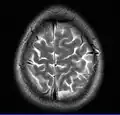

Brain regions on T1 MRI -

- T2-weighted (T2W) images: CSF is light, but fat (and thus white matter) is darker than with T1. T2-weighted images are useful for visualizing pathology.[26]